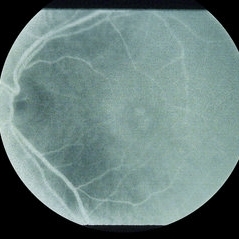

The right fundus showed 3+ dry age related maculopathy with 4/10 cupping of the optic nerve and a normal periphery. The left fundus showed a cystic appearance to the left macula, 4/10 cupping of the optic nerve, and a negative periphery.

Fluorescein angiography shows an unusual form of cystoid edema in the macular region. His vision has remained the same over a seven-month period with no response to treatment.

Cystoid Macular Edema (CME)